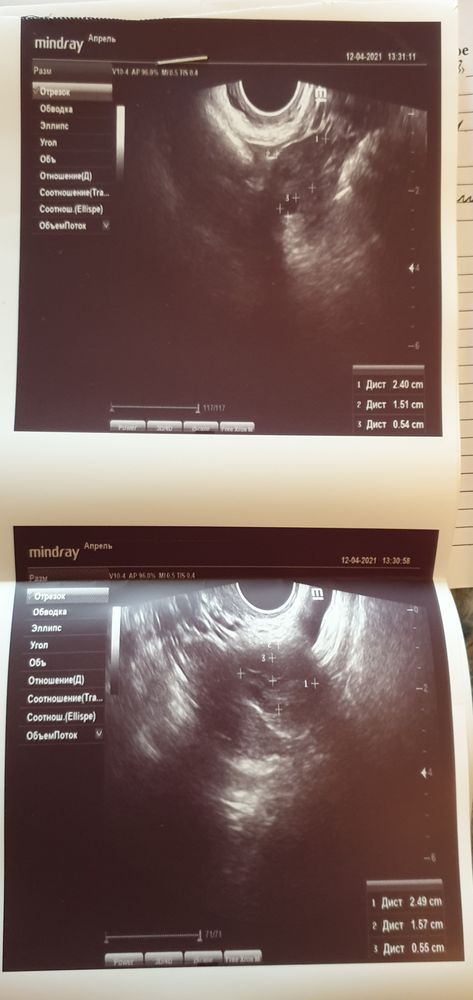

Добрый день, девочки) У меня в этом цикле опять большая задержка, пошла делать узи в платную клинику. Узи какое-то смазанное впечатление оставило, делала не больше 1,5 минут. Врач сказала, что эндометрий пышный, что у нее ощущение, что должны скоро пойти месячные. Я спросила, значит была овуляция, она ответила, что не знает, т.к. нет свободной жидкости. Девочки, разве может быть эндометрий 11 мм без овуляции? Про желтое тело спросить не сообразила, может оно уже угасло? Мне это важно, т.к. я считала длинные циклы ановуляторными. Все звала меня к себе на консультацию, как к гинекологу-эндокринологу. Написала аденомиоз под вопросом, в целом сказала, что ничего страшного нет по узи. Вы бы пошли к такому врачу наконсультацию?

У вас яичники без жт и не увеличены. Всё таки если было/есть жт яичник по размеру был бы больше